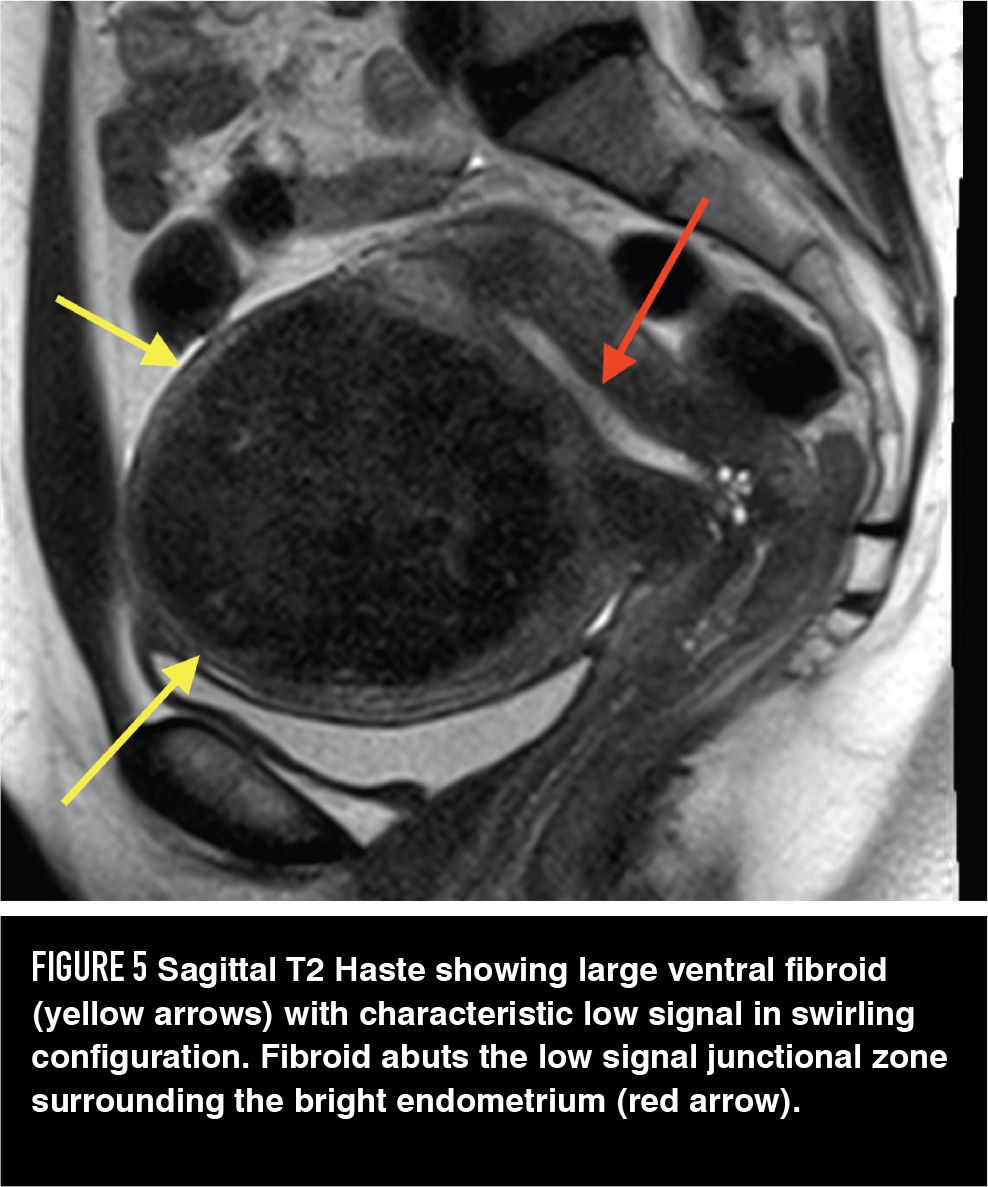

Figure 5